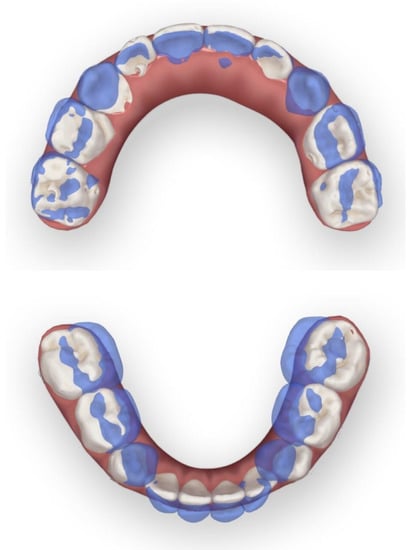

The clinical examination revealed a convex profile with protrusion of the upper and lower lips and hypertonia of the lip muscles (Figure 1). An intraoral examination identified a primary dentition phase. Centric occlusion examination indicated a Class III terminal molar relationship with a bilateral posterior scissor bite. The left posterior teeth presented a complete scissor bite with no contact on the occlusal surface, which was worse than their right counterparts (Figure 2 and Figure 3). An anterior crossbite was observed with a reverse overjet and overbite. Furthermore, the jaw could be retracted to display an edge-to-edge bite when guided backward. The mandibular incisors were upright, with the upper incisors slightly lingually inclined. The upper and lower dental midlines were aligned with the facial midline. No functional mandibular shift was observed when the mouth was open, and no clicking or pain was detected in the TMJ area. Moreover, habitual mandibular protraction at rest and during speech was observed.

The patient and his parents allowed the use of his medical records, photographs and radiographs in this research. Prior to the initiation of therapy, panoramic and lateral cephalometric films were obtained. The panoramic radiograph showed swelling in the bilateral nasal mucosa (Figure 4). A mild skeletal Class II sagittal relationship (ANB = 5.4°) and large mandibular plane angle (SN-MP = 39.8°) were indicated in the pre-treatment cephalometric film (Table 1). Meanwhile, his hyoid (MP-H) rested lower than normal (16.8 mm, mean normal = 14.2). In addition, he had a hyperdivergent growth pattern (facial height index, S-Go/N-Me = 57.9%). The airway width assessment showed that he had a limited nasopharyngeal airway gap and expanded oropharyngeal segments (data shown in Table 1). His adenoids were diagnosed with moderate hypertrophy (Figure 5) with an A/N of 64.5% [11,12], which was derived from an adenoidal–nasopharyngeal ratio (AN ratio) via linear measurements using lateral radiographs of the nasopharynx according to Fujioka et al. and Zou. et al. [11,12]. Considering that adenoids in children are physiologically enlarged between 2 and 12 years of age, Zou proposed that an A/N ratio of 0.60 should be considered as normal; 0.61–0.70 is considered as moderate hypertrophy; ≥0.71 is considered as pathological hypertrophy [12]. The digital models’ STL files were uploaded to the Geomagic Studio 12.0 software (Research Triangle Park, NC, USA) for measurement (Figure 6 and Figure 7). The statistics concerning the widths of the dental arch and basal skeletal, as well as the height, surface area and volume of the palatal, are displayed in Table 2.

Figure 2. Initial digital study models.

Figure 3. View of scissor bite details of the initial digital models.